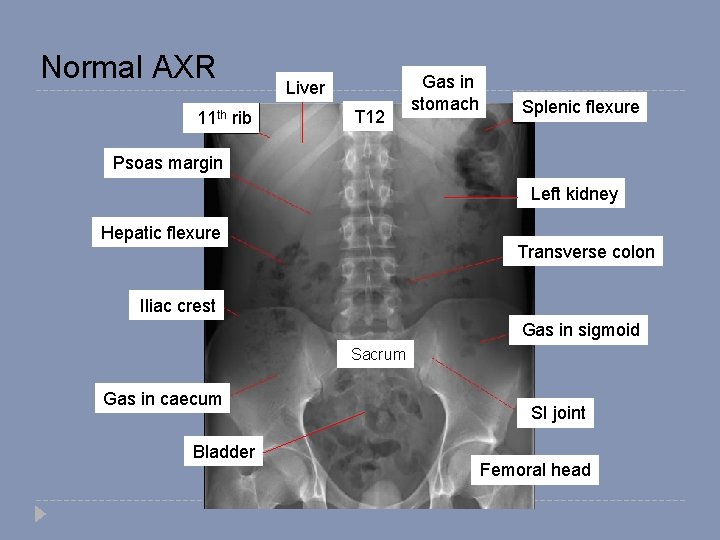

Normal AXR

Normal AXR 11 th rib Liver T 12 Gas in stomach Splenic flexure Psoas margin Left kidney Hepatic flexure Transverse colon Iliac crest Gas in sigmoid Sacrum Gas in caecum Bladder SI joint Femoral head